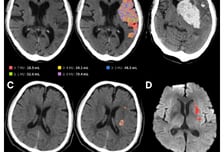

제이엘케이, 북미영상의학회 참가…美 파트너십 논의 본격화

의료 인공지능(AI) 기업 제이엘케이가 한국보건산업진흥원의 글로벌 전시회 지원 프로그램을 통해 이번 달 미국 시카고에서 열리는 '2025 북미영상의학회(Radiological Society of North America 2025·RSNA 2025)'에 참가한다고 27일 밝혔다. RSNA 2025는 오는 30일부터 다음 달 4일까지 미국 일로노이주 시카고 맥코믹 플레이스에서 진행된다. 전 세계 100여 개국, 5만명 이상의 의료 전문가가 집결하는 영상의학 분야 최대 규모의 국제 학회로, 의료 AI 기업에게는 북미 시장 진출의 핵심 무대로 꼽힌다. 이번 학회에서 김동민 대표는 'AI 기반 뇌졸중 진단 워크플로우 개선: JLK 인공지능 솔루션을 활용한 실제 임상 적용 사례(Optimizing Stroke Workflow Using AI: Real-World Applications of JLK's Stroke Imaging Solutions)'를 주제로 발표를 진행한다. 이 발표에서 김 대표는 제이엘케이의 뇌졸중 AI 영상 분석 솔루션이 실제 임상 환경에서 어떻게 활용되고 있는지에 관해 설명하는 동시에 진단 정확도 향상, 치료 결정 시간 단축, 진단 워크플로우 개선 등에 AI 기술이 어떤 기여를 하는지를 다기관 연구와 임상 논문 결과로 제시할 예정이다.